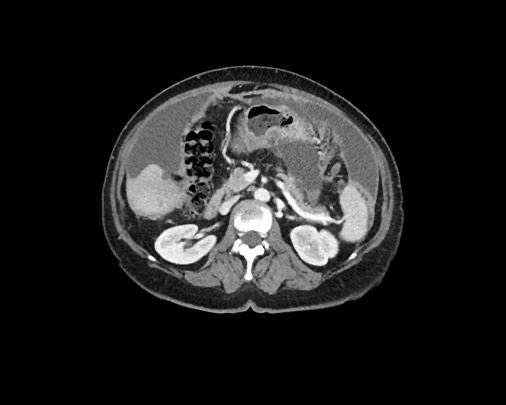

Ca lâm sàng 2

Cuộn qua các lát cắt.

Bạn có thể phát hiện tất cả các tổn thương cấy ghép phúc mạc không?